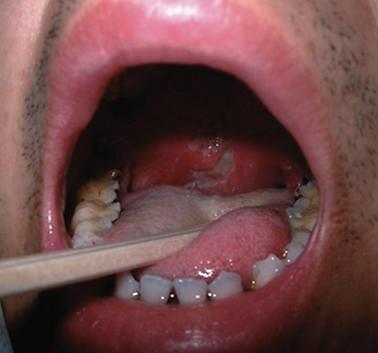

白塞病口腔溃疡,白塞病症状生殖图片

白塞氏病是一种全身性免疫系统疾病,同时或先后发生的口腔粘膜溃疡

白塞病症状生殖图片

白塞病图片

白塞病的症状

口腔溃疡图片症状

口腔溃疡真实图片